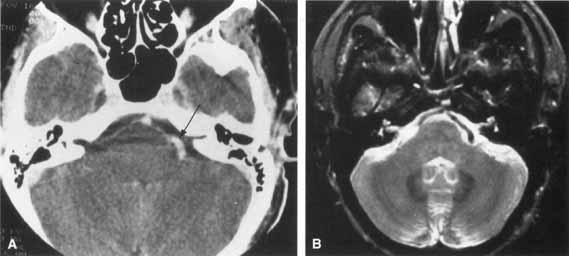

Lyme disease may cause unilateral or bilateral facial paralysis (Fig. 12).53 This disease is characterized by erythema chronicum migrans, tick-borne meningopolyneuritis, myocardial conduction abnormalities, and Lyme arthritis. The disorder was first recognized in 1975 by close geographic clustering of children with arthritis in the small community of Lyme, Connecticut. The spirochete B. burgdorferi is transmitted by an arthropod vector (the deer tick, Ixodes dammini). The skin lesion begins as a red macule or papule and expands to form a large red ring with partial central clearing. The lesion typically lasts about 3 weeks or longer (Fig. 13). Associated symptoms include malaise, fatigue, chills, fever, headache, myalgias, nausea, vomiting, and sore throat. Some patients develop a spectrum of neurologic symptoms and a clinical picture suggesting collagenosis, syphilis, or multiple sclerosis.

Fig. 12 Axial T1-weighted, gadolinium-enhanced MRI showing bilateral proximal facial nerve enhancement (arrows) in patient with Lyme disease and facial diplegia.

Cranial neuropathies occur frequently in Lyme disease; facial nerve palsy is the most common of these. Unilateral or bilateral facial nerve palsies occurred in 11% of patients with Lyme disease in one series.53 In the United States, facial palsy is observed in half the patients with Lyme meningitis. The prognosis for facial nerve recovery with or without therapy is excellent, with the majority of patients achieving satisfactory facial function. Despite the frequent spontaneous resolution of the facial paresis, therapy should be administered to prevent the late neurologic and arthritic complications that can occur. Interestingly, facial nerve paralysis occurs with or without CSF pleocytosis. Distinguishing Lyme-associated facial palsy from idiopathic (Bell's) palsy is essential. Lyme disease is suggested when there is coexisting multiorgan involvement such as cardiac disease or arthritis. Fever, enlarged lymph nodes, pharyngalgia, and headache are more common with Lyme disease than with Bell's palsy.54 Nontender swelling and erythema of the face before the onset of the facial palsy may also be a distinguishing feature of Lyme disease.55